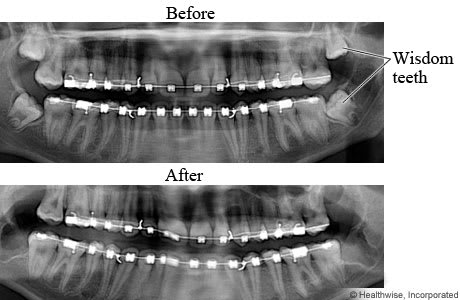

X-rays of mouth before and after wisdom teeth removal.

Wisdom teeth are the upper and lower third molars, located at the very back of the mouth. In some people, wisdom teeth are crowded and difficult to clean properly. They may also push against other teeth. In these cases, the wisdom teeth can be extracted (removed).